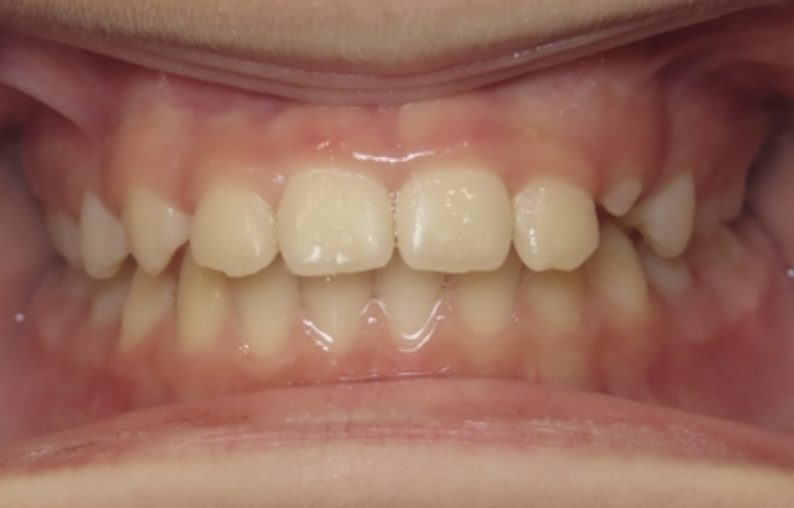

Protrusion

Upper teeth stick out beyond the lower teeth.